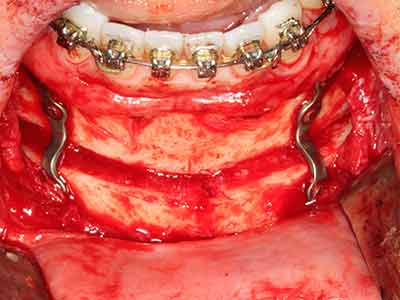

Костната тъкан е не само минерализирана структура, тя съдържа и съществено количество колагенови влакна. Това означава, че тя има не само добра компресивна сила, но и известна степен на гъвкавост, която може да се възприеме като предимство при извършване на костна аугментация. В класическата процедура по разширяване чрез костно разделяне, атрофиралият алвеоларен гребен е разделен надлъжно и внимателно разширен след достигане на подходящата остеотомна дълбочина (Фиг. 13-16), в идеалния случай без допълнително отстраняване на периостеума (Brugnami, Caiazzo et al. 2014, Stricker, Fleiner et al. 2014). Системите с винт и пластини с увеличаване на разстоянието при разширяване са доказали ефективността си при разделяне на двете костни ламели, оставайки под прага на фрактурите. В общи линии, оставащата ширина на костта от поне 3–4 mm е задължителна (Chiapasco, Zaniboni et al. 2006), за да се гарантира добра гъвкавост и достатъчно костно покритие за бъдещото поставяне на импланти. Ако е необходимо, вертикалната остеотомия на едната или двете страни може да подобри гъвкавостта. Комбинацията с допълнителни техники за аугментация, особено в букалната страна, е описана като алтернатива на класическата техника.

Процедурата по разделяне е атравматична и няма голяма загуба на пространство, използвайки пиезотриони, и няма значителна разлика между импланти в разделени челюсти и импланти в алвеоларния гребен без костен дефицит (Chiapasco, Zaniboni et al. 2006, Danza, Guidi et al. 2009). Въпреки това, важно е да има достатъчно и продължително охлаждане, особено при ограничено и дълбоко разделяне, за да се избегне термичен стрес в апикално-остеотомните зони.